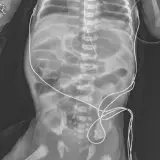

Over 2,100 interactive radiology cases, curated by radiologists for your level of training. Scroll, window, and view cases full screen โ€” just like on PACS. Click linked findings in each writeup to jump straight to them on the image. Cases include sample reports, a focused discussion section, original illustrations, and videos.

Call Preparation โ€” our comprehensive curriculum for junior residents preparing for call covering both classic and atypical presentations. Use the call simulator to practice a real call shift โ€” shuffle cases, enter your own preliminary report, and receive constructive AI feedback.

Casi completamente interattivi con gli strumenti che ti aspetti su un PACS: scroll, windowing, zoom, pan, misurazioni, ROI e modalitร  a schermo intero.

Annotazioni dettagliate evidenziano i reperti chiave direttamente sui casi. Clicca sui reperti collegati nella descrizione del caso per saltare alla loro esatta posizione sullo scan.